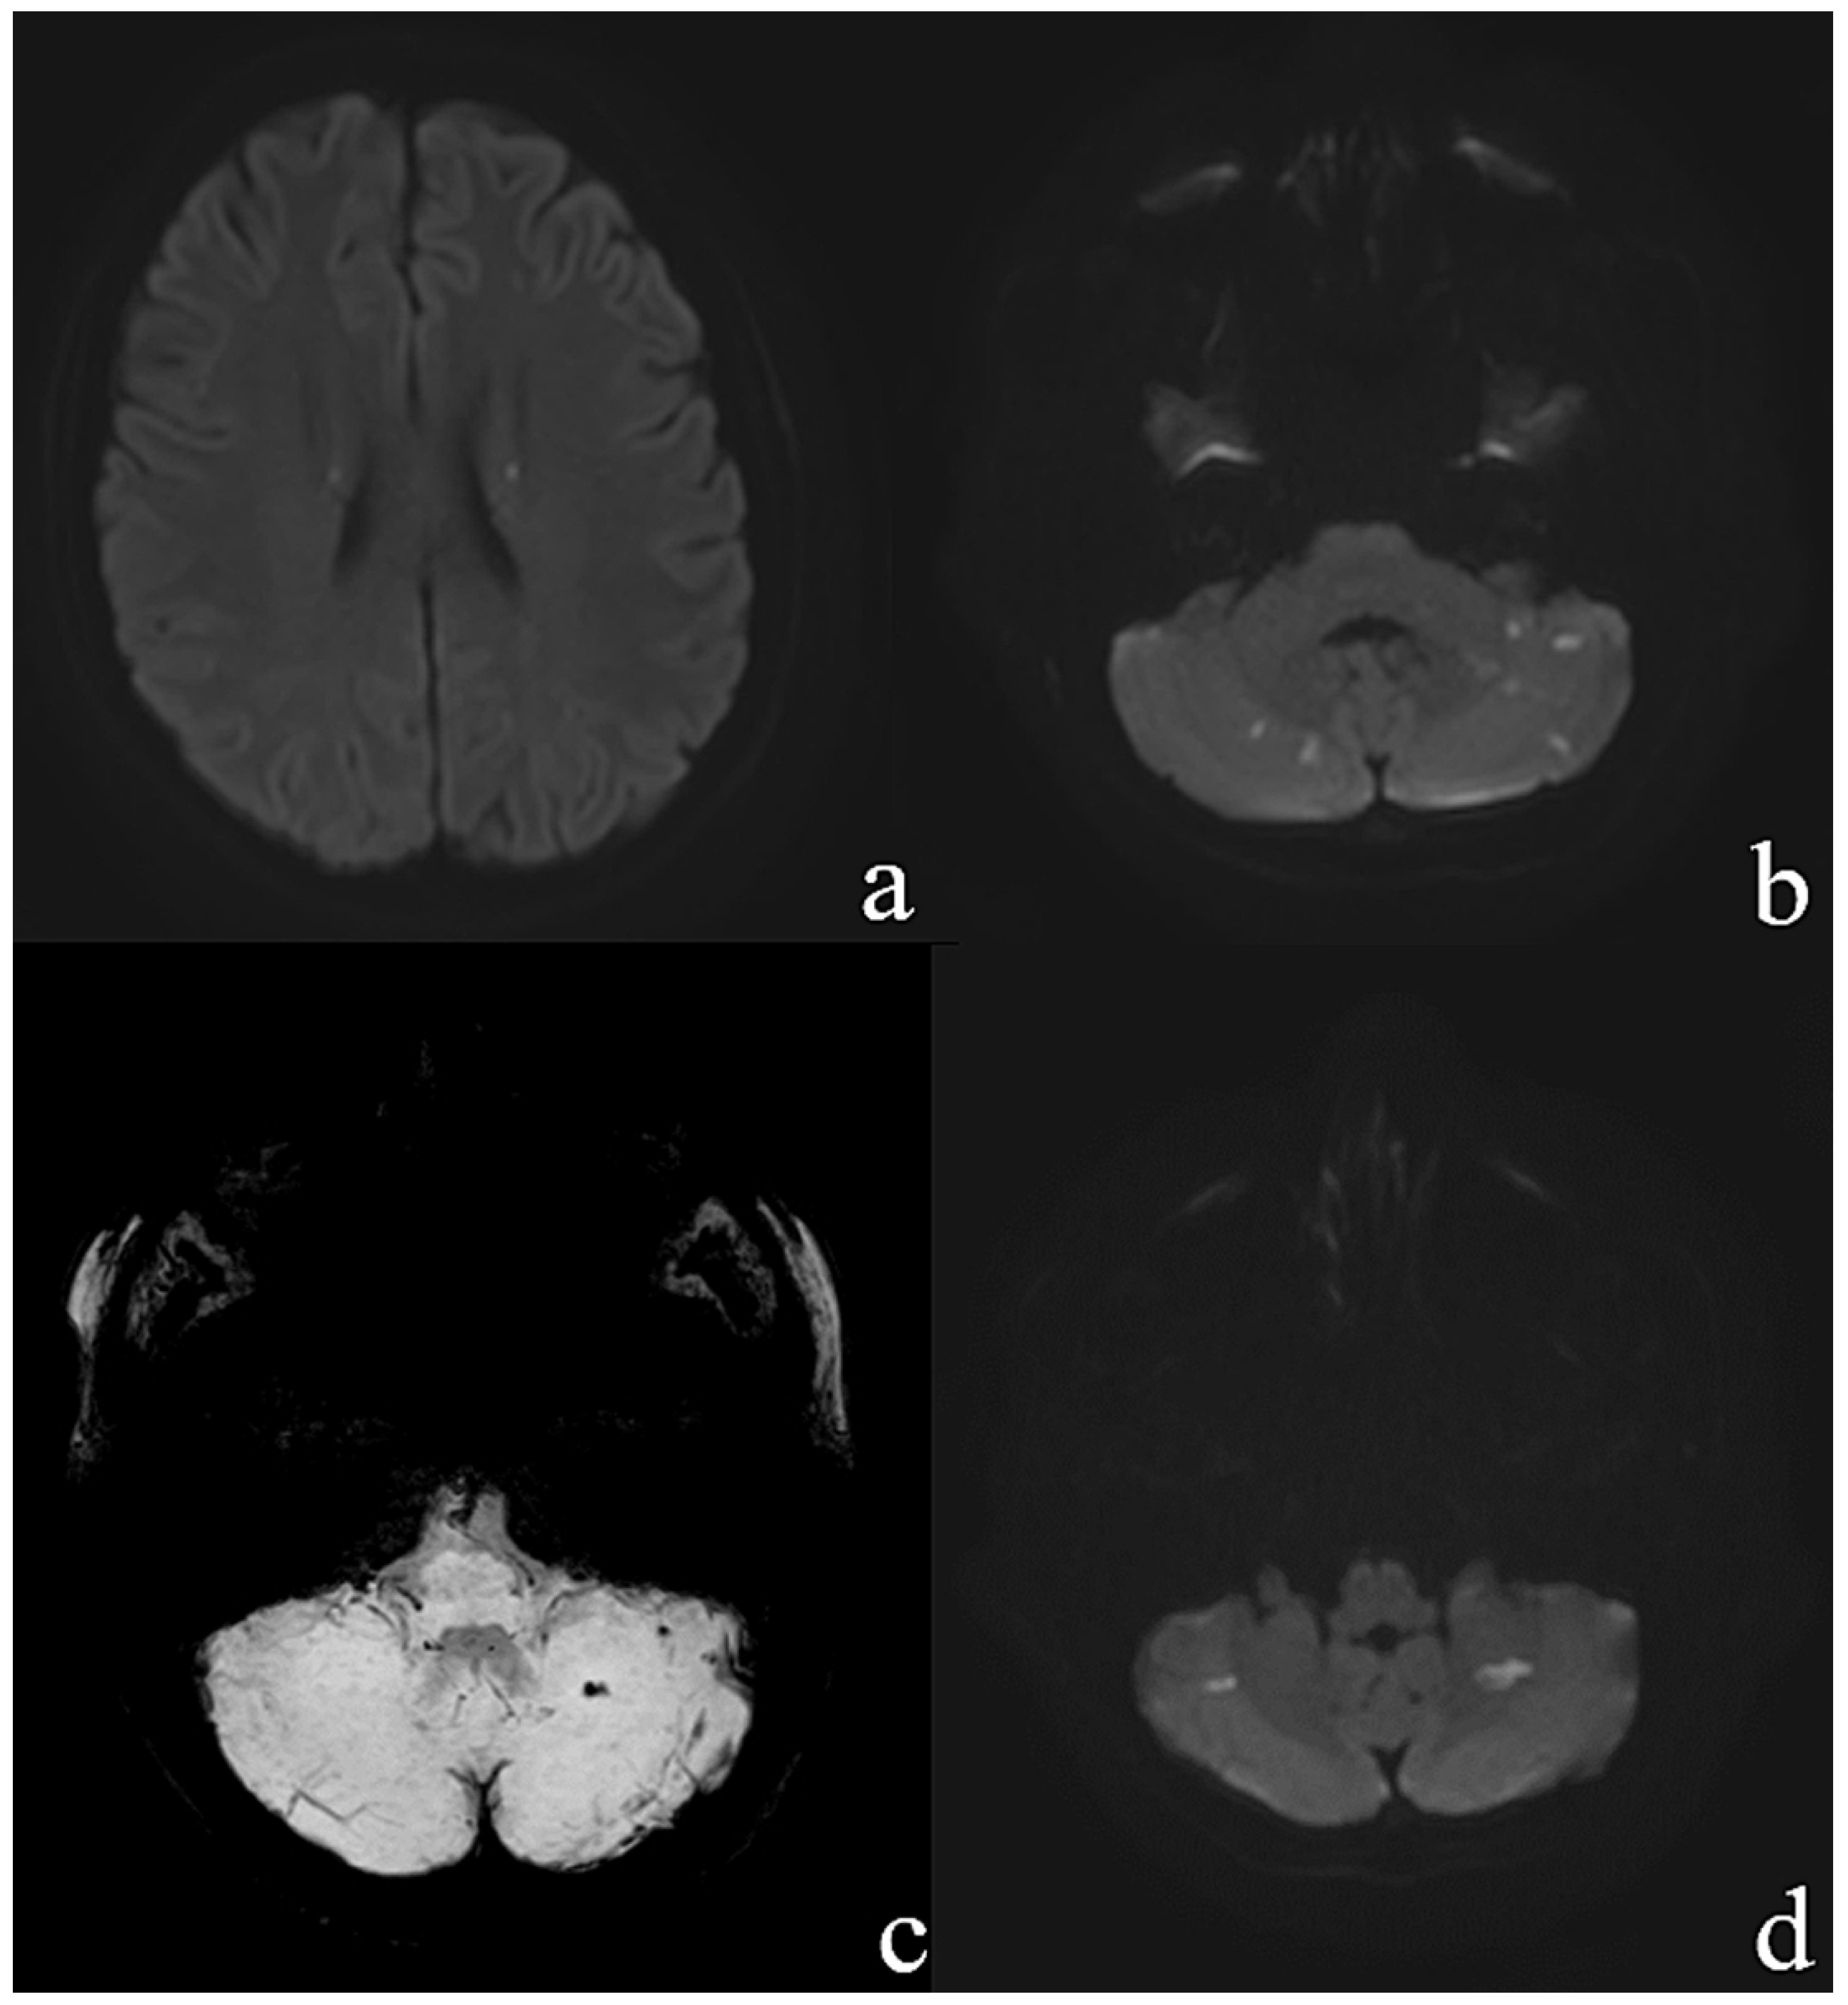

Large Native Mitral Valve Vegetation in a Previously Healthy 19-Year-Old Woman